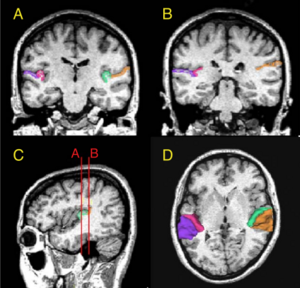

MRI with labeled structures from atlas registered to the CBCT. Registration was carried out with the open source imaging tool 3D Slicer, Version 4.4.0. |